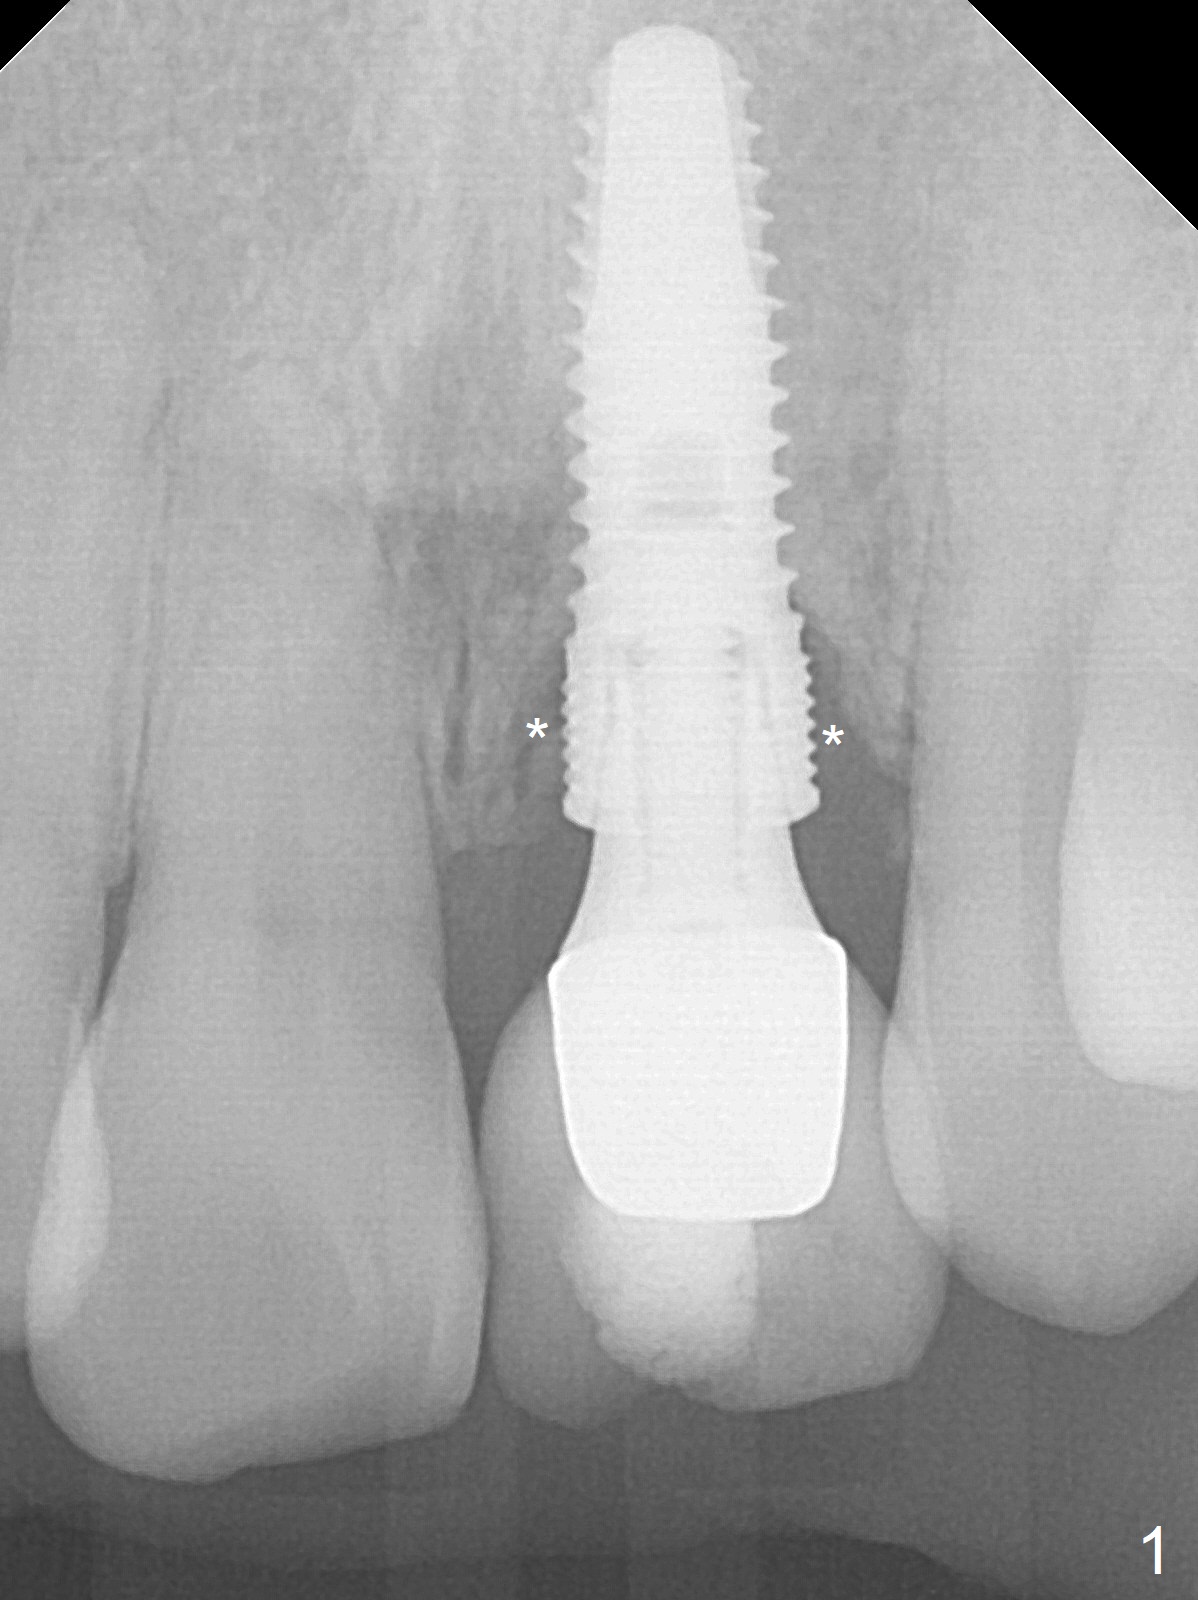

A 56-year-old woman finally agrees to redo the implant (4.5x14 mm) with repeated screw loosening and periimplantitis (chief complaint "gum bleeding while using Water Pik", Fig.1).  To reduce the 1st complication, a 1-piece implant will be chosen.  To decrease the 2nd one (i.e., to place the implant deep), an abutment with 4 mm cuff will be used.  To achieve primary stability, initiate osteotomy in the apical bone ~ 3 mm.  Autoclave 2 endo stoppers and use the longest 1.5 mm drill or one from 1-piece kit with a drill extension.  After implant removal (Metronidazole), measure the osteotomy depth using drill stopper and probably the soft tissue landmark and drill for 3 mm.  If the total depth is 20 mm, a 3x16(4) mm 1-piece implant will be used.  Also prepare UF kit (Fig.2) in case primary stability cannot be achieved with the 1-pience one.  Place a piece of Osteogen tape against the buccal wall, pack Vanilla graft around the implant and use a piece of collagen plug to seal the osteotomy (socket).  Use 4-0 Chromic gut suture to close the opening so that there will be no escape of the bone graft.  Periodontal dressing will be applied.  However, use an anterior metal tray to take Alginate preop in case of implant placement failure.  Also take preop photos to show the erythematous buccal gingiva.  Take 5x5 CT postop if needed.  In addition to using curette to remove fibrotic granulation tissue from the osteotomy after implant removal, use 15% EDTA gauze (x3 times) to kill remaining bacteria remaining in the osteotomy.  Draw blood for PRF if blood vessels are not too thin.